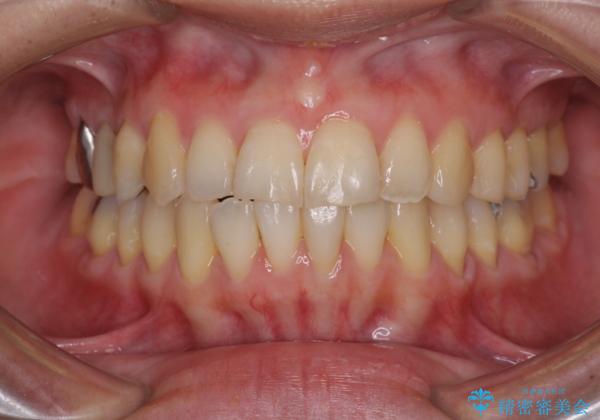

切端咬合をインビザライン矯正で解消

- 前歯のデコボコを気にして来院された患者様です。

上下前歯の先端同士が接触する切端咬合であったため、上顎は歯列を拡大し、下顎はIPR(歯と歯の間を削る)により叢生を解消しながら歯列を小さくすることとしました。

矯正装置にはインビザラインを用いることとしました。

治療途中に前歯に歯髄充血を思わせる痛みが認められたため、無理のない歯の移動と頻繁な経過観察を行いました。

切端咬合はスムーズに解消され、前歯の負担を軽減させることができました。